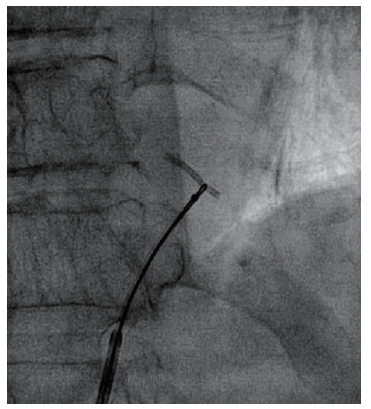

A LAD stent migrates retrogradely into the aortic root crossing the left main ostium. Image source and courtesy Hilary Bews and others, Coronary stent on the move, European Heart Journal – Case Reports, Volume 5, Issue 12, December 2021, ytab511, https://doi.org/10.1093/ehjcr/ytab511